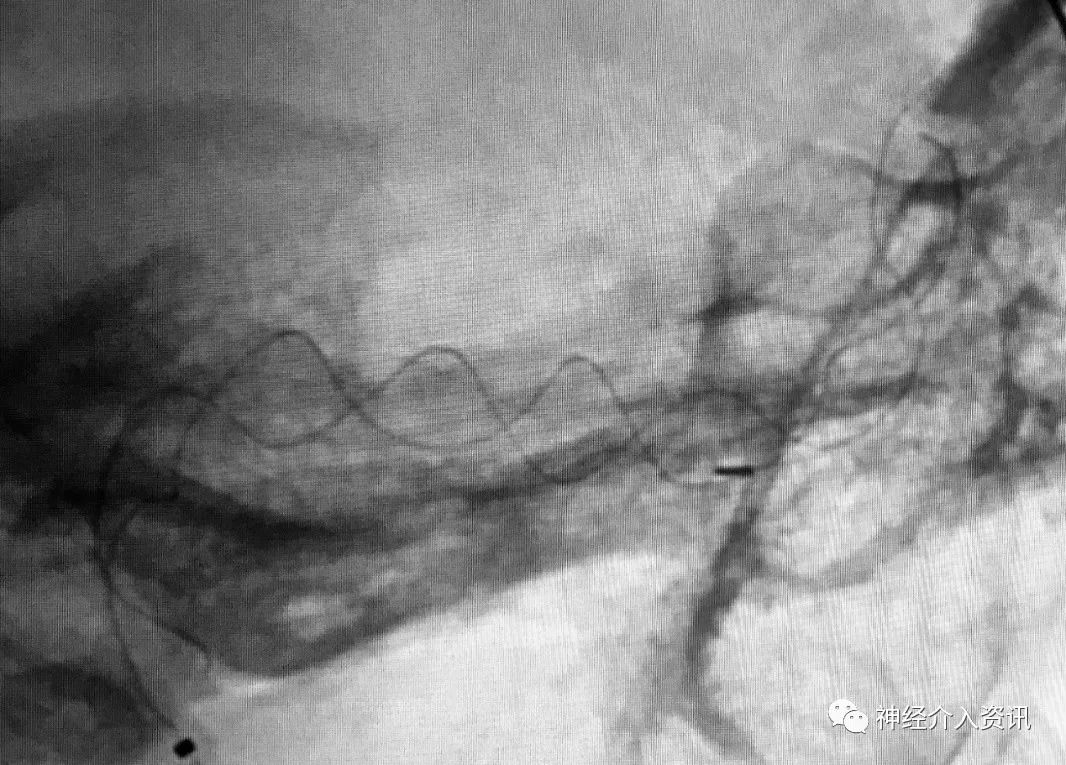

图2:血管重建装置释放后,其龙骨显影提示整个装置打开良好,完全贴覆于血管内壁上,并将受累节段血管完全覆盖。